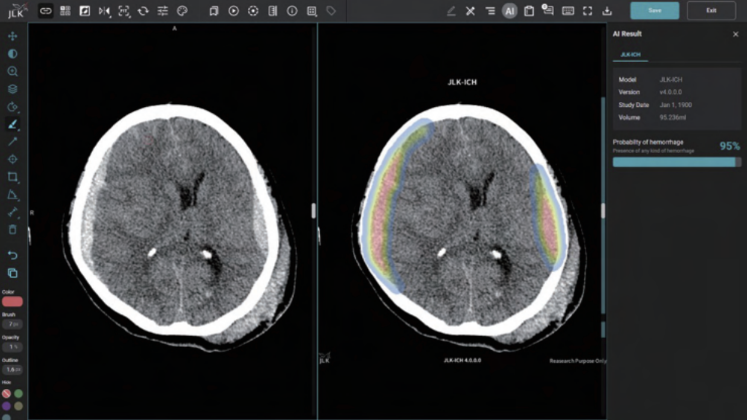

JLK-ICH는 환자의 뇌 컴퓨터단층촬영(CT) 영상을 분석해 뇌출혈 영역을 검출하는 인공지능(AI) 솔루션이다. 통상 뇌졸중 의심 환자가 응급실에 도착하면 가장 먼저 뇌 CT를 촬영해 뇌출혈 여부를 확인하는데 회사는 이 과정에서 JLK-ICH가 쓰일 것으로 예측한다.